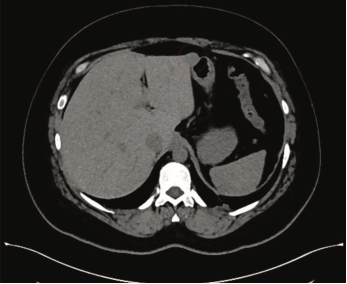

Figura 2 Estudio de tomografía computada abdominopélvica en fase simple; se señala la lesión hepática (círculo punteado) en correlación con la imagen obtenida durante la laparoscopia

Paciente del sexo femenino, de 47 años de edad, que al inicio de una cirugía bariátrica laparoscópica abdominal, durante la inspección de la cavidad abdominal y su contenido, se evidenció una lesión focal hepática, lo que representó un hallazgo incidental (figura 1), por lo que se decidió suspender el procedimiento y evaluar dicha